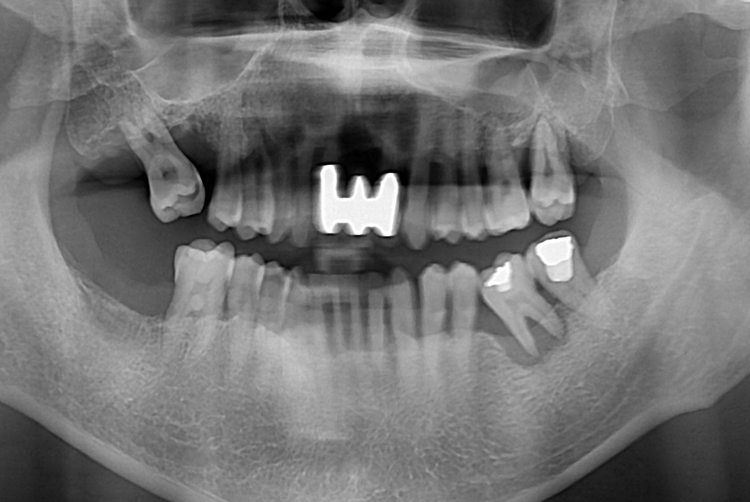

[임플란트] 어금니 임플란트

치료후 : 2017-09-27

세종치과는 많은 환자와 다양한 케이스를 바탕으로

항상 편안한 임플란트 수술을 제공하고자 노력하고,

오래동안 튼튼히 쓸 수 있는 임플란트 수술을 가장 큰 목표로 삼고 있습니다.